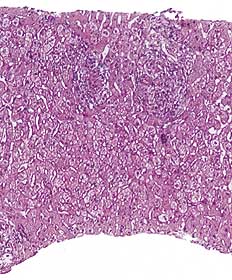

Pasient 1 . 50 år gammel kvinne. Frisk inntil januar 1999. Etter dette to epileptiske anfall med noen måneders mellomrom. Behandling med karbamazepin (Trimonil Retard ) ble iverksatt og over to uker gradvis opptrappet til 300 mg ⋅ 2. Hun brukte ingen andre medikamenter. 18 dager etter oppstart med karbamazepin ble pasienten febril og følte seg slapp, etter hvert ble hun plaget av hodepine, kvalme og oppkast. Symptomene var økende, og fem dager senere ble hun innlagt i medisinsk avdeling. Ved innkomst var hun våken og klar, ikke nakkestiv, intet utslett. BT 150/85 mm Hg, puls 84 regelmessig, temperatur 38,2  ˚C. Normal organstatus. Spinalvæskeundersøkelse var upåfallende. Blodprøver viste leverpåvirkning forenlig med akutt parenkymatøs leverskade (tab 1). Karbamazepin ble mistenkt som mulig årsak og derfor seponert. Etter få dager ble pasienten symptomfri. Det ble utført leverbiopsi, som viste akutt og kronisk betennelse med granulomer (fig 1). Det var ikke holdepunkt for viral hepatitt eller autoimmun leversykdom, idet både virusserologiske undersøkelser (antistoff mot hepatitt A-virus, hepatitt B-virus, hepatitt C-virus, cytomegalovirus og Epstein-Barr-virus) og autoantistoffer (antinukleært antistoff (ANA), antistoff mot glatt muskel og antistoff mot mitokondrier) var negative. Immunglobulinene (IgA, IgG og IgM) var også innenfor normalområdet. Ultralyd lever viste intet patologisk. Blodprøver tre måneder senere viste full normalisering av leverenzymer.

Medikamentell hepatitt er ofte en eksklusjonsdiagnose. Våre pasienter ble undersøkt for en rekke kjente leversykdommer uten at noen ble påvist. Det var ikke mistanke om overforbruk av alkohol hos noen av pasientene. Etter oppstart med karbamazepin var det for pasient 1 og pasient 2 latenstid på henholdsvis 18 og 14 dager før symptomene meldte seg. Hos alle pasientene var det rask tilbakegang av symptomer og normalisering av biokjemiske parametere etter at medikamentet ble seponert. Ingen hadde s-karbamazepin over terapeutisk område, to av pasientene var febrile og en hadde artralgier. Ingen hadde eosinofili, men i en av de to leverbiopsiene som ble utført, ble det påvist granulomer (fig 1). Disse funn er forenlig med det som er referert tidligere i litteraturen (6, 8).